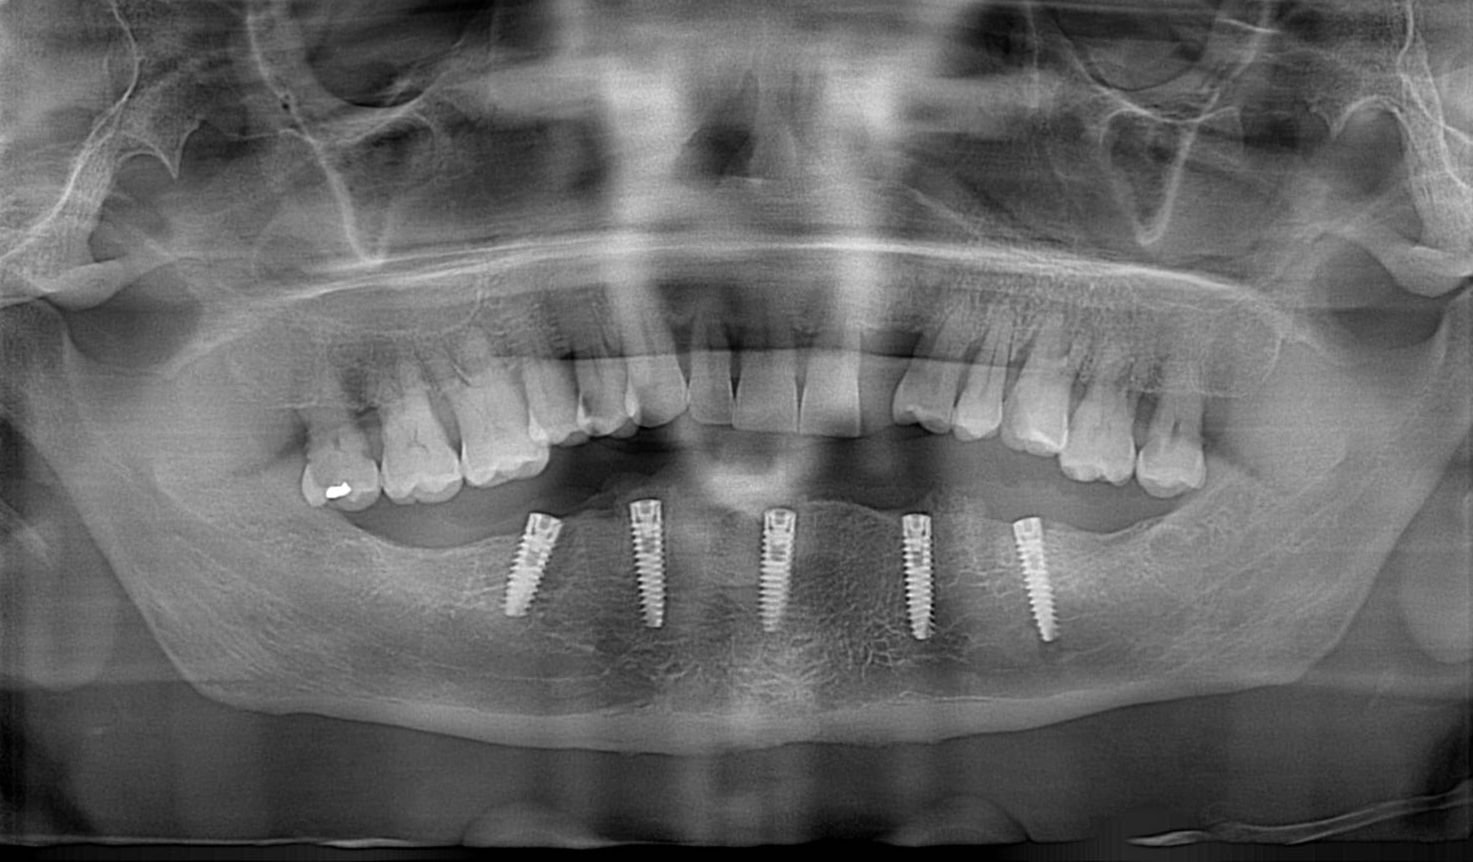

La rehabilitación oral combina diferentes tratamientos dentales para restaurar dientes dañados, reemplazar piezas perdidas y mejorar la mordida, devolviéndote la seguridad de sonreír y masticar sin problemas.

Con especialistas certificados y tecnología moderna, diseñamos un plan de rehabilitación oral a tu medida.